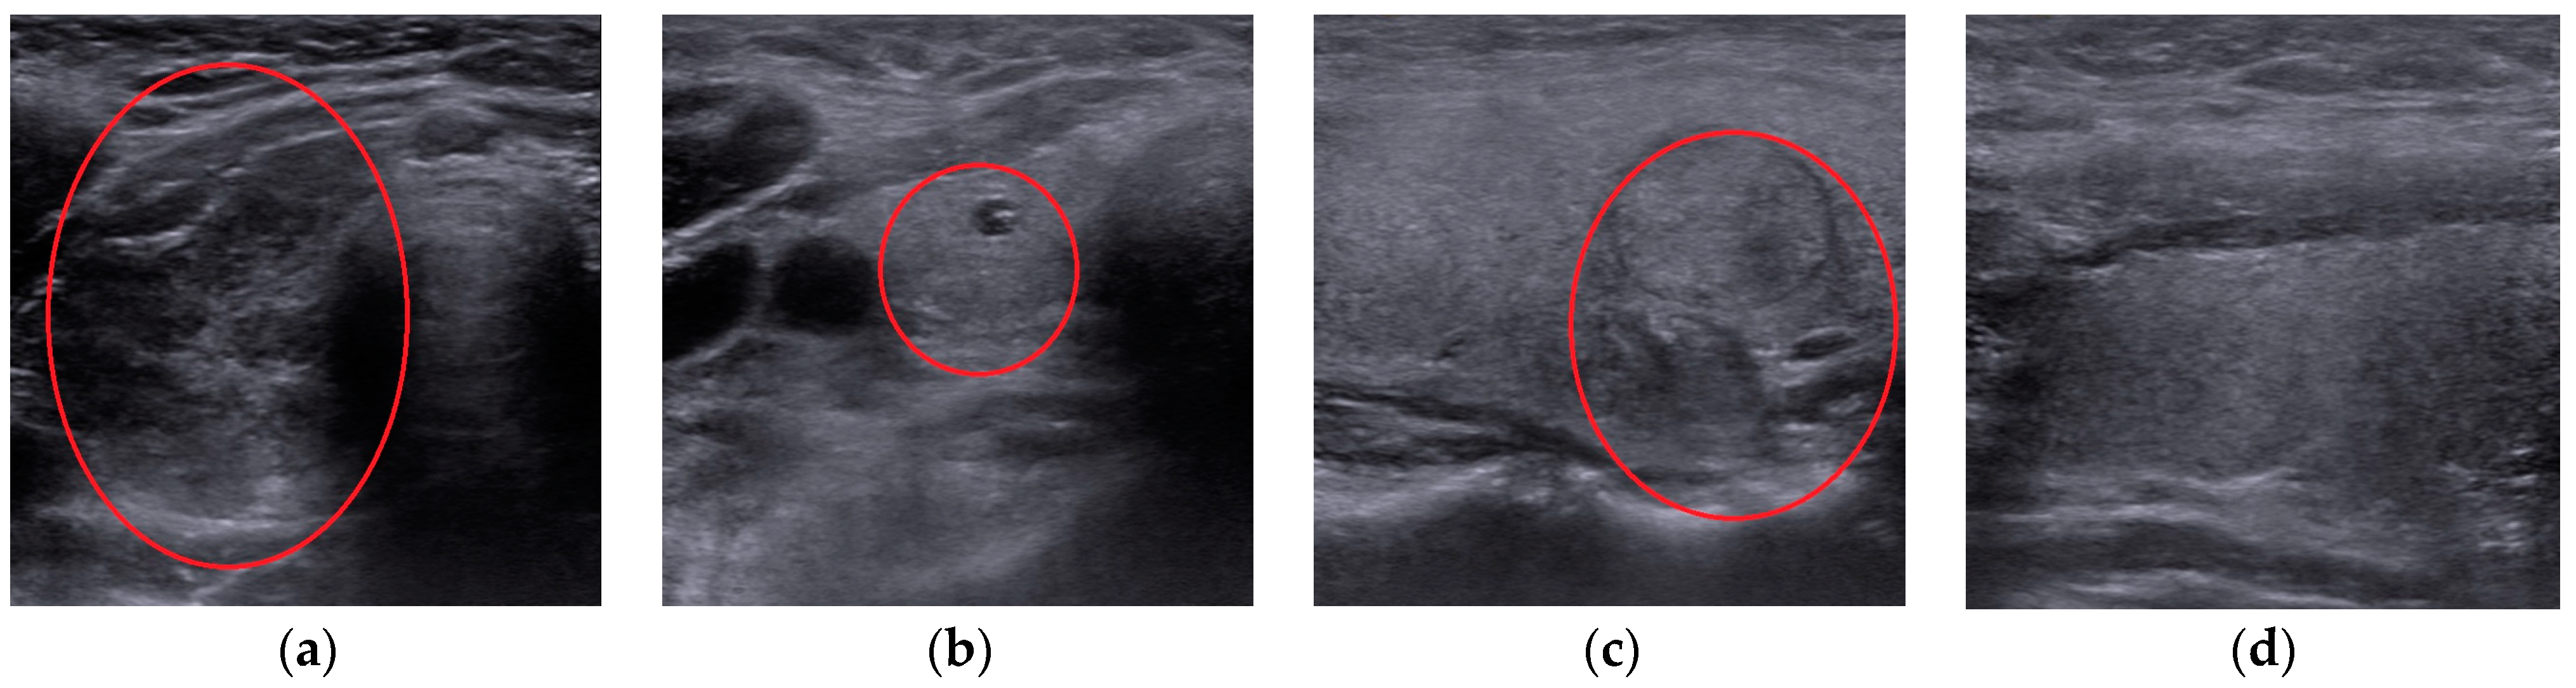

- Collecting and curing a novel dataset of 2797 images, which included thyroidal US images, classified into four diagnoses: autoimmune, micro-nodular, nodular, and normal.

2.2. Image Dataset